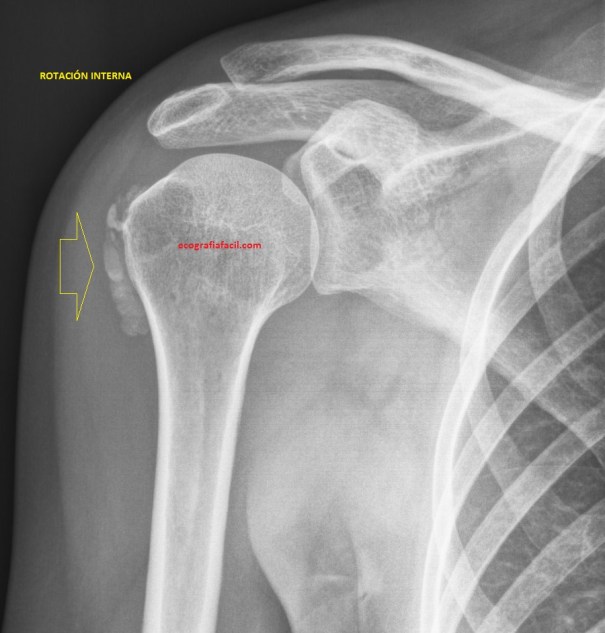

Para los médicos de atención primaria y otros especialistas o para los fisioterapeutas, el dolor de hombro, la omalgia, es un problema ya que el diagnóstico diferencial es amplio. Cada vez más se está sustituyendo la clásica Rx de Hombro por ecografía muscular para descartar patología. En este caso, fue así, realizamos primero la ecografía, pero posteriormente la radióloga pidió ampliar con rx de hombro.

Habitualmente en el protocolo de hombro podemos ver calcificaciones insercionales, entensopatías, en subescapular y en supraespinoso como localización habitual, en esta última localización son muy habituales calcificaciones groseras, incluso la tendinopatía calcificante.

En la paciente del caso que hoy nos ocupa existían calcificaciones, pero estas no se encontraban localizadas en su lugar habitual, con las imágenes lo vas a ver todo mejor…mira:

Has visto estas cuatro imágenes. La imagen 1 es la normalidad absoluta, la imagen 2 es una calcificación grosera con sobra acústica posterior en la porción media del supraespinoso en el corte transverso. En la imagen 3 y 4 puedes ver una calcificación en la región externa del hombro, es una localización poco habitual y la radióloga tras realizar la rx de hombro, como ves en la imagen 5 y 6, determinó  que las calcificaciones habían migrado desde su localización habitual en el supraespinoso, situándose entre el hueso y el deltoides (imagen 7).

Si observas, existen diferencias entre ambas calcificaciones, la más evidente desde el punto de vista semiológico es que hay calcificaciones que dejan una sombra posterior evidente, otras, como las que nos ocupan en este post, no tienen el artefacto de sombra posterior, esto es debido a las diferentes densidades de calcio y esto es muy habitual en la eco MSK. En la imagen 3, la sombra es muy sutil y se observa bajo la línea hiperecogénica del húmero (flecha grande y amarilla de la imagen 7).

En la imagen 6 ves un conglomerado de calcios con la proyección interna, marcados por flecha amarilla fina, apenas visibles en la Rx en rotación externa, muy importante siempre ambas rotaciones cuando buscamos calcios.